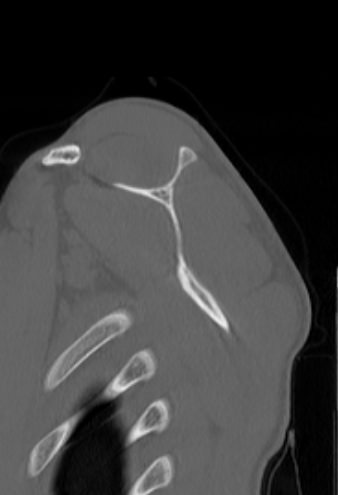

Наиболее информативным методом диагностики патологии плече-лопаточной области является мультиспиральная компьютерная томография. КТ относится к лучевым методам исследования, то есть для получения изображения внутренних органов применяется рентгеновское излучение, которое лучше всего подходит для изучения плотных структур, в частности, костных тканей. В процессе исследования томограф послойно сканирует область лопатки при помощи проникающей способности рентгеновских лучей, затем с помощью компьютерных приложений данные преобразуются в наглядные трехмерные изображения исследуемых органов.

Аппараты сканируют область исследования в течение нескольких секунд, производя одномоментно от 64 до 128 тончайших срезов толщиной от 0,5 мм. Высокая скорость сканирования обеспечивает минимальную дозу облучения для пациента. При этом получаются четкие изображения с высоким контрастным разрешением, что дает возможность рассмотреть исследуемую зону в мельчайших подробностях. Кроме того, томографы создают объемные 3D-изображения области лопатки и прилегающих органов и тканей, что помогает в оценке пространственного соотношения анатомических структур, выявленной патологии и способствует проведению точной диагностики.